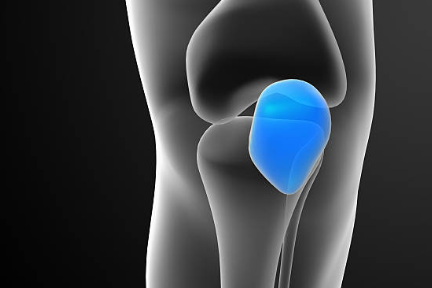

3. 골관절염

골관절염은 관절의 연골이 마모되어 관절 간의 마찰이 증가하는 질환입니다. 골관절염이 발생하면 무릎 안쪽 통증이 발생하며, 부기, 딱딱한 소리, 관절의 움직임 제한 등의 증상이 동반될 수 있습니다. 골관절염은 나이가 들면서 자연적으로 발생할 수 있으며, 비만, 과도한 운동, 외상 등의 요인이 영향을 줄 수 있습니다.

7. 내측 콘드롬

내측 콘드롬은 무릎 안쪽의 연골이 마모되어 관절의 안정성이 떨어지는 질환입니다. 내측 콘드롬이 발생하면 무릎 안쪽 통증이 발생하며, 부기, 무릎의 불안정감, 관절의 움직임 제한 등의 증상이 동반될 수 있습니다. 내측 콘드롬은 과도한 운동, 비만, 외상 등의 요인으로 인해 발생할 수 있습니다.